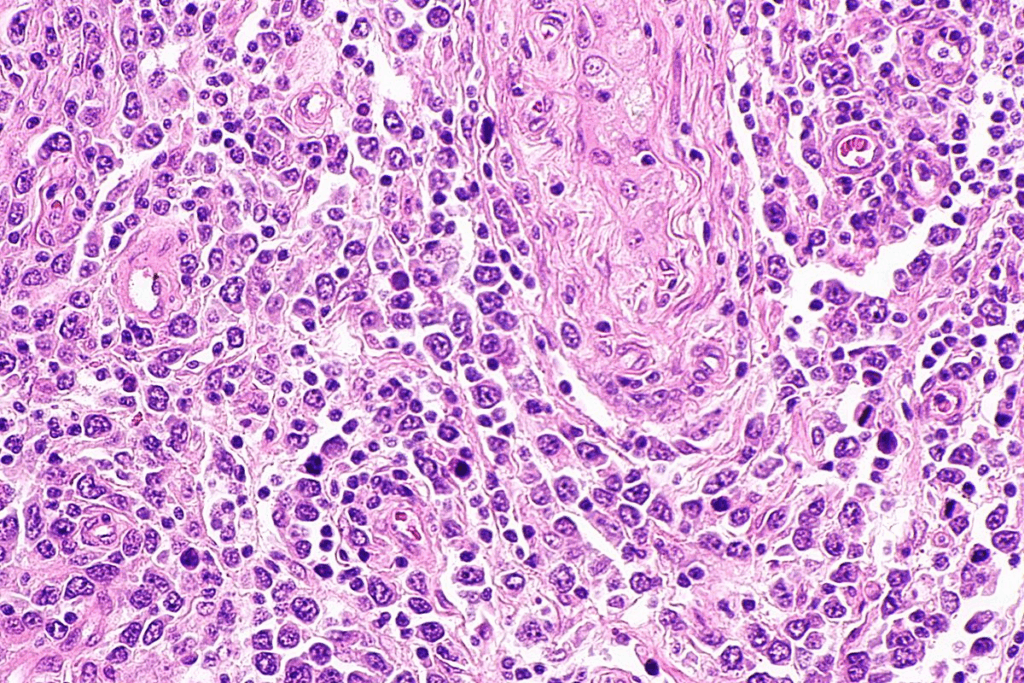

Pathophysiology of Advanced Adenomyosis

Stage 4 adenomyosis happens when endometrial glands and stroma move into the uterine muscle. This messes up the normal uterine tissue. It leads to inflammation, scarring, and a big uterus.

The endometrial tissue grows into the myometrium and reacts to hormones. This causes bleeding in the uterine wall. It leads to more inflammation and damage.

Diagnostic Imaging: What Stage 4 Adenomyosis Looks Like

Knowing what Stage 4 adenomyosis looks like on imaging is key for correct diagnosis and treatment. Ultrasound and MRI are vital for spotting this condition’s signs.

Ultrasound Findings

Ultrasound shows Stage 4 adenomyosis as thickened myometrium with unclear edges. Myometrial cysts are common, appearing as dark or light spots in the myometrium. The area between the endometrium and myometrium may also look thick and uneven.

MRI Characteristics

MRI gives a clearer view of adenomyosis, mainly in Stage 4. It shows how much of the myometrium is affected and how thick the junctional zone is. On MRI, adenomyosis looks dark on T2-weighted images. Myometrial cysts appear bright on T2-weighted images.